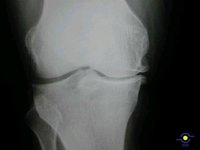

Las lesiones de rodilla multiplican el riesgo de artrosis

De hecho, un estudio publicado en la revista 'Clinica Sports Medicine' ha mostrado que las lesiones del ligamento cruzado anterior, de las más habituales en el deporte, están relacionadas con el desarrollo de artrosis --u osteoartritis-- de rodilla.

En dicha investigación, los expertos han comprobado que las mujeres que practican deportes y otras actividades en las que se pivota sobre la rodilla tienen "entre 3 y 5 veces más posibilidades" de sufrir una lesión del ligamento cruzado anterior que los hombres. Además, el dolor y la discapacidad asociada se presentan entre 10 y 15 años después de la lesión, por lo que son más frecuentes a la edad de 30 y 50 años. Por ello, han solicitado estrategias para la prevención de estas lesiones y la consecuente artrosis.